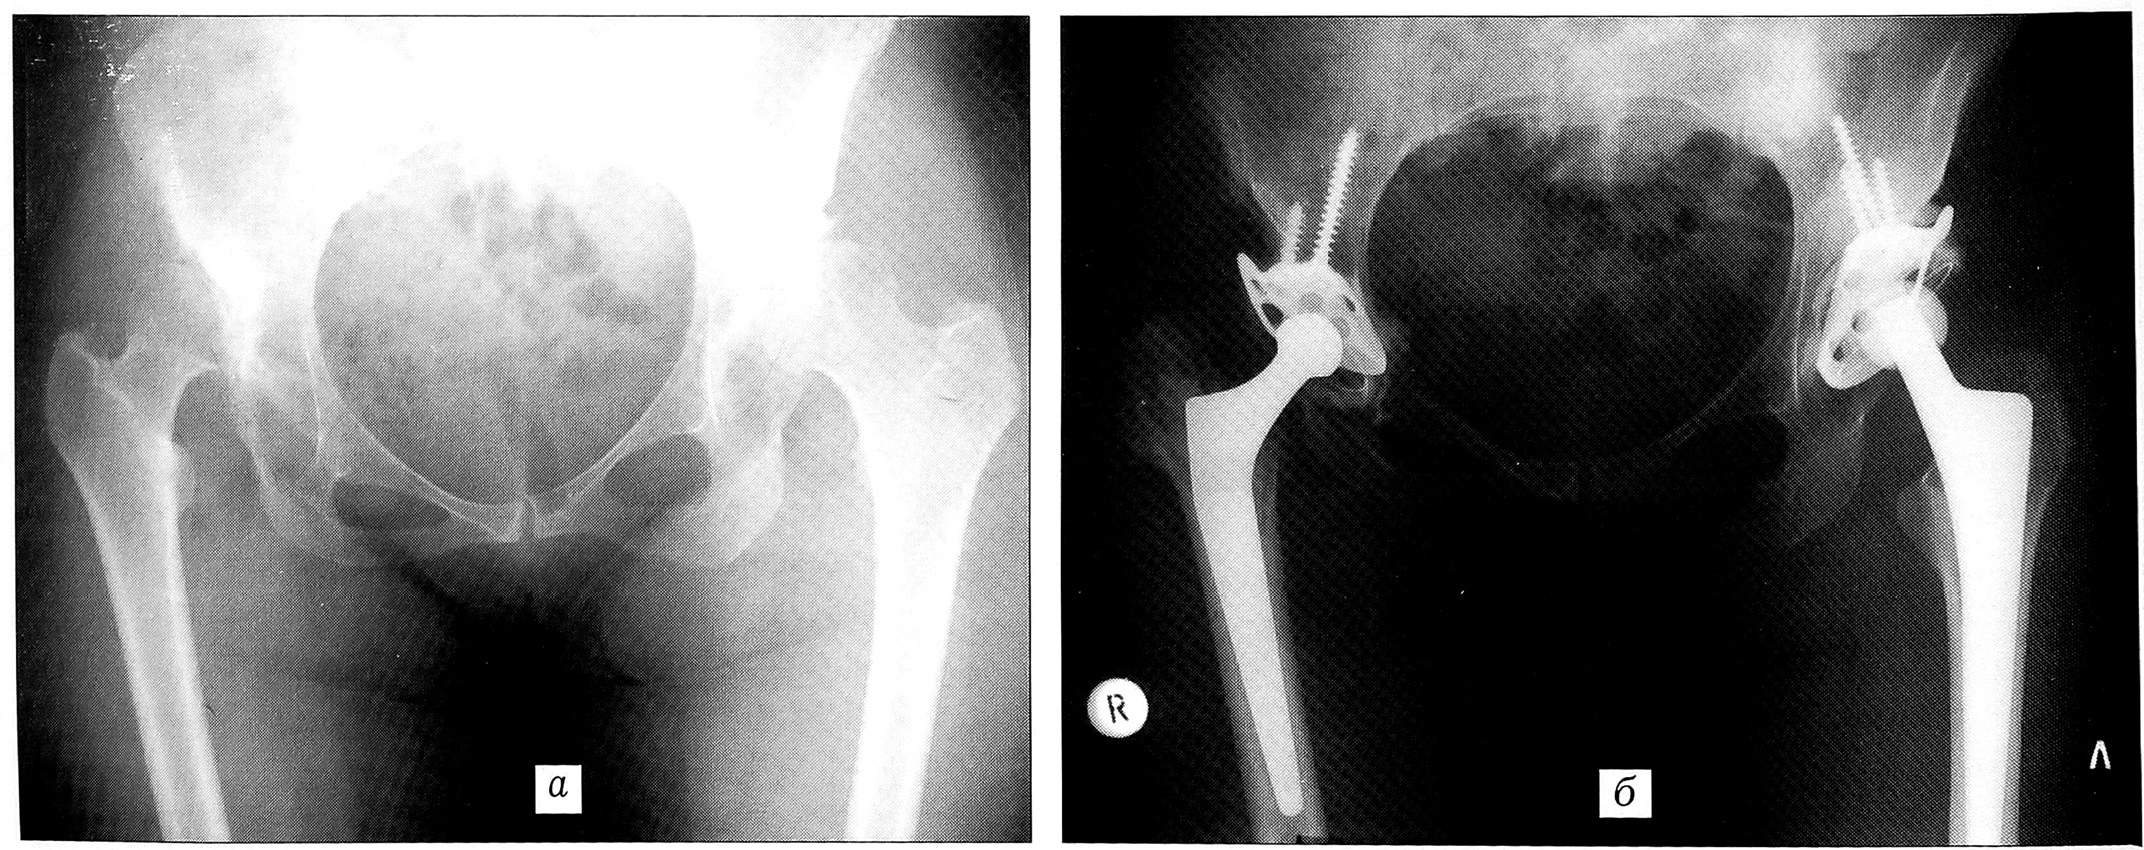

Рис. 2. Рентгенограммы больной К. 42 лет. Диагноз: врожденный вывих обоих бедер с абсолютным укорочением конечностей (правой — на 5,5 см, левой — на 3 см).а — до операции; б — через 1 год после операции на левом и 1,5 года — на правом тазобедренном суставе.

Больная К., 42 лет. Диагноз: врожденный вывих обоих бедер с абсолютным укорочением правой конечности на 5,5 см, левой на 3 см (рис. 2, а). Произведено двустороннее эндопротезирование тазобедренных суставов с интервалом в 6 мес. Справа: укрепляющее кольцо Мюллера и диспластическая цементируемая ножка Мюллера; слева — укрепляющее кольцо Мюллера и бесцементная ножка Споторно. Восстановлены длина и функция оперированных конечностей (рис. 2, б). Срок наблюдения 8,5 лет после операции на правом и 8 лет — на левом суставе: хорошая остеоинтеграция ацетабулярного и бедренного компонентов эндопротезов, пациентка работает по своей специальности (зоотехник).